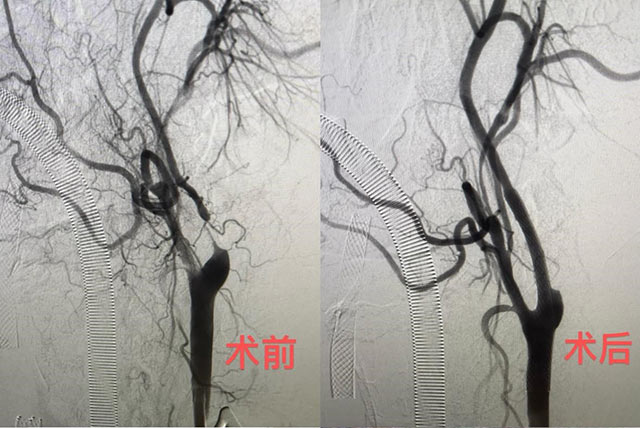

68岁的张伯(化名)因枕部头痛、耳鸣多次住院,三年前被查出右侧颈动脉80%重度狭窄,并在右侧放了两个支架;当时左侧则是50%中度狭窄程度,并未放置支架。三年后,张大叔左侧病情又进展到重度,1.2厘米血管已经狭窄达90%,几乎断流。在与患者充分沟通的基础上,6月11日,广东省人民医院专家团队实行了这项新技术。6月13日,张伯顺利出院。

TCAR技术在华南地区成功开展,为颈动脉狭窄患者的治疗增添了新的选项及更优的选择。据介绍,新术式具有小伤口、微创、不经过主动脉弓、更有效过滤的优势;同时,避开颅神经损伤,以及逆向血流保护和更低的心肌梗死、脑梗死发生率等优势,30天围手术期总卒中发生率低至1.4%,让颈动脉狭窄的治疗更加安全有效。